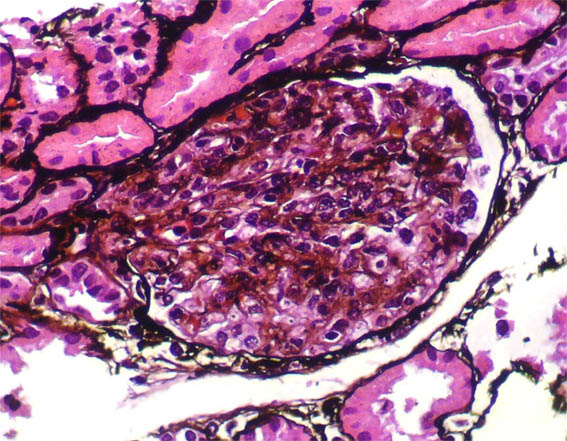

Figura 6.

Plata-metenamina, X400.